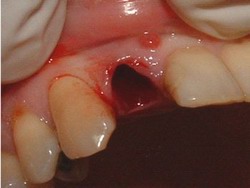

Imagen 2: Lecho óseo respetando tej. Blandos

Imagen 3: Curetaje del lecho óseo